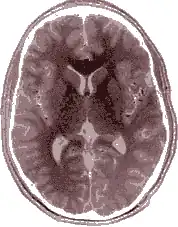

Erkenntnisse aus Untersuchungen zur Lateralisation des Gehirns zeigen, dass überwiegend die linke Hirnhälfte für die motorische Steuerung der rechten Körperseite und die rechte Hirnhälfte für die der linken Körperseite zuständig ist.

Als „dominante“ Hirnhälfte wird diejenige bezeichnet, die vorrangig für die Verarbeitung von Sprache zuständig ist.[27] Bei 95 % der Rechtshänder befindet sie sich links, bei 2 % rechts. Bei 3 % ist das Sprachzentrum auf beide Hirnhälften aufgeteilt. Auch bei der Mehrzahl der Linkshänder liegt das Sprachzentrum links, nämlich bei 70 %, bei 15 % ist es auf beide Hemisphären verteilt, bei weiteren 15 % liegt es rechts. Es gibt also eine gewisse Korrelation zwischen der „dominanten“ Gehirnhälfte und derjenigen Gehirnhälfte, die die starke Hand steuert. Dennoch liegt das Sprachzentrum bei der Mehrzahl der Linkshänder auf der linken Seite, welche für die „schwache“ rechte Hand zuständig ist. Es liegt also keine eindeutige Gesetzmäßigkeit vor in der Verbindung von Händigkeit und Lateralisation des Gehirns. Wenn man einen Anteil von 10 % Linkshändern voraussetzt, liegen bei etwa 7 % der Bevölkerung die Steuerung der „starken“ Hand und das Sprachzentrum in verschiedenen Gehirnhälften – ohne dass Nachteile entstehen.[28]